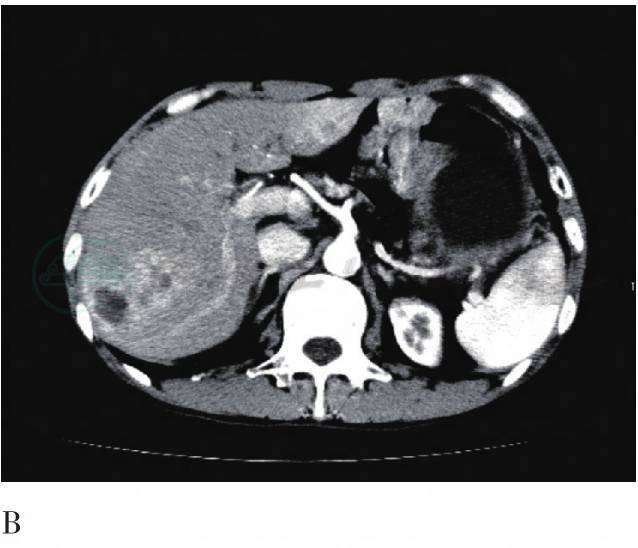

图2 FDG PET/CT横断层图

A. CT平扫;B. CT增强扫描动脉期;C. CT增强扫描门脉期;D. PET/CT融合图像。肝内可见多发稍低密度灶,最大者大小约3.3cm×4.1cm,病灶放射性摄取不均匀增高,SUVmax值为8.4;动脉期明显强化,高于周围肝组织,门脉期强化程度低于周围肝组织